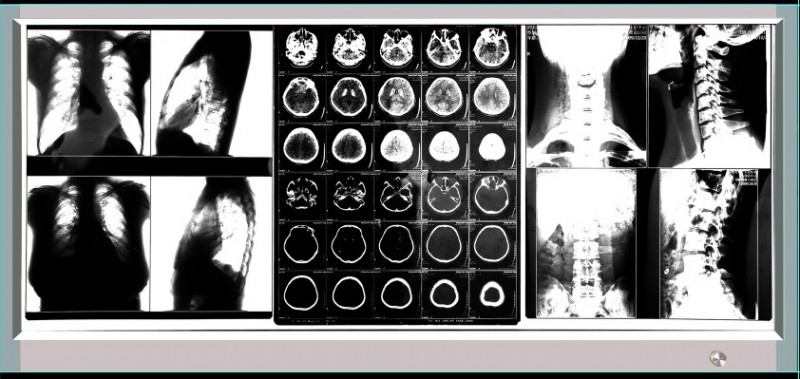

LED4000三联调光型观片灯,观察屏的亮度为300-4000cd/m2可调,能阅读普通模拟片、数码拷贝片及钼靶乳腺片。能同时观察三张14*17的胶片。观片灯的外形尺寸:1128*509*22.5mm ,观察屏尺寸:1068*422mm。